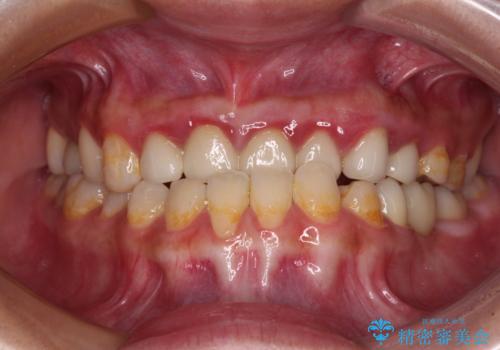

根管治療や歯周外科処置後にフルジルコニアクラウンにて補綴治療することとしました。

自身の口腔内への意識が高くなく、汚れが非常に多い方でした。

再発や他の歯がむし歯となるリスクを低減させるため、日頃からのプラークコントロールと定期的なクリーニングが重要となります。